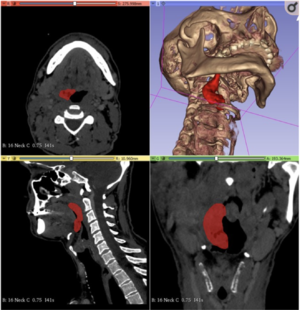

3D Slicer and Sina Appilication for Surgical Planning of Giant Invasive Spinal Schwannoma With Scoliosis: A Case Report and Literature Review

Publication: Neurochirurgie. 2020 Nov;66(5):396-399. PMID: 32777234 Authors: Hou X, Yang DD, Li D, Zeng L, Li C. Institution: School of Clinical Medicine, Chengdu University of TCM, Hospital of Chengdu University of Traditional Chinese Medicine, Chengdu, China. Abstract: The surgical management of giant invasive spinal schwannomas (GISSs) has been discussed previously, and most cases are treated via the posterior approach. However, when the tumor grows beyond the spine and greatly pushes the surrounding tissues, the combined anterior-posterior approach may be a better choice. However, the anterior approach can be challenging when there is a lack of knowledge regarding the surrounding abdominal structures. Case description: A 67-year-old male suffered from slight scoliosis and an unstable spine due to GISS, which led to a long history of lower back pain and abnormal gait. Here, we report a novel method combining the use of 3D Slicer and the Sina application to help surgeons locate such lesions and better understand the three-dimensional (3D) relationship between the tumor and surrounding tissues. The proposed method promotes complete excision, shortens operation time, and reduces related complications. Conclusion: We recommend using the combination of 3D Slicer and Sina to assist surgeons in handling accurate 3D information of GISS while simultaneously simulating the surgery. |